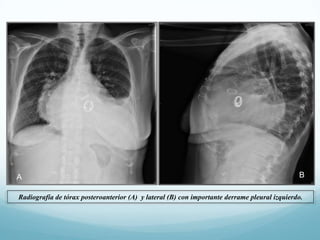

Radiografía de tórax posteroanterior (A) y lateral (B) con importante derrame pleural izquierdo.

A B Radiografía de tóraxposteroanterior (A) y lateral (B) con importante derrame pleural izquierdo.